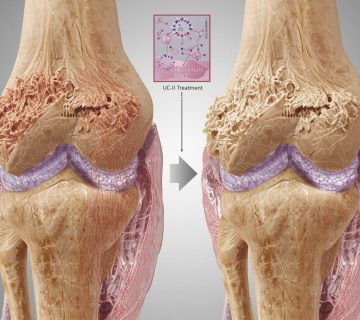

- غضروف مفصلی: کاهش تخریب غضروف، کاهش اندازه استئوفیت ها و حفظ ماتریکس غضروف در گروه UC- II مشاهده شد.

- استخوان زیرغضروفی : UC-II از کاهش تراکم استخوان اسفنجی جلوگیری کرد.

مصرف خوراکی UC-II بلافاصله پس از آسیب، میتواند با حفظ عملکرد مکانیکی مفصل، از تخریب بیش از حد غضروف جلوگیری کند. این یافته ها از کاربرد UC-II به عنوان یک گزینه درمانی کمکی در استئوآرتریت حمایت می کنند.